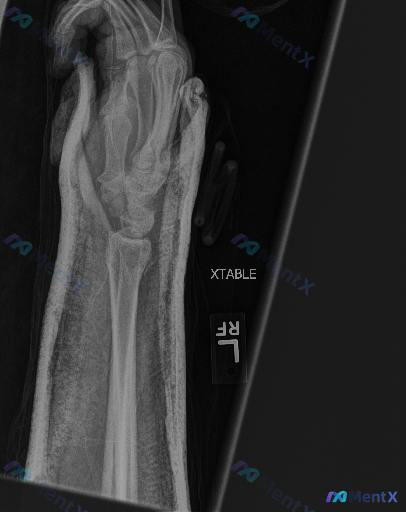

右手前臂外伤后X光片:这组影像表现最核心的异常是什么?

整理到一份右手前臂及手部X光斜位片的影像资料,背景是急性外伤后,主要影像表现如下:

- 骨骼方面:桡骨远端可见明显骨折线,断端有移位及成角畸形,皮质连续性中断;尺骨茎突位置也见骨折断端,有移位;掌骨及近节指骨可见范围内未见明确骨折线。

- 关节方面:腕关节解剖结构因骨折发生改变,关节面移位、对合关系紊乱。

- 软组织方面:局部软组织轮廓增宽、密度增高,存在肿胀;影像中可见部分外部固定物/敷料影。

- 骨密度方面:整体骨密度尚可,未见明显广泛性骨质疏松或溶骨性破坏征象,也无明显骨赘、骨膜反应。